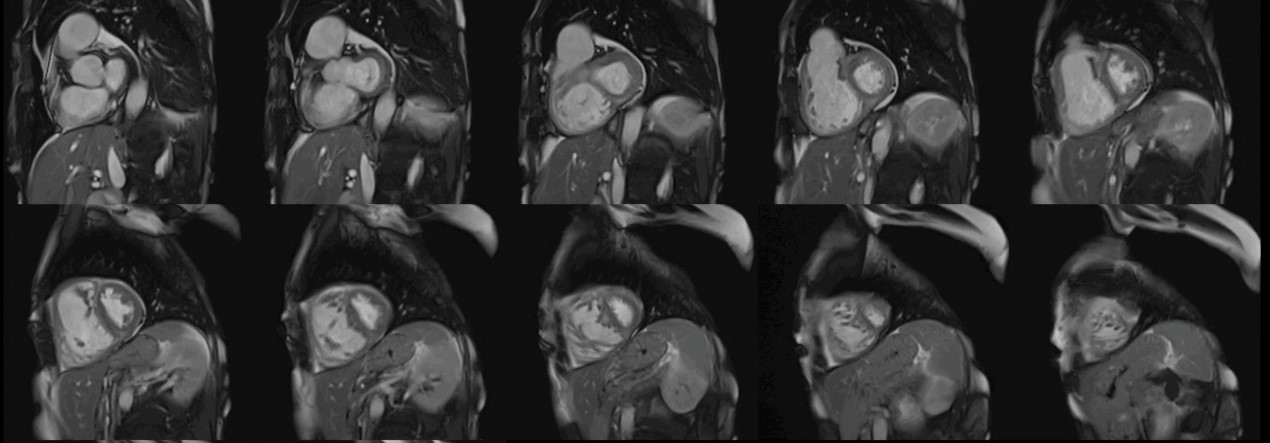

The CMR pulse sequence used for assessment of cardiac function is the balanced steady-state free precession (bSSFP). It represents the gold standard for the evaluation of cardiac anatomy, mass, wall motion, and right/left atrial/ventricular dimensions and function [11]. This is of particular value in patients with autoimmune disease, where RV pathology can play an important role in the generation of VAs and may not be adequately imaged using echocardiography [11] (Fig. 1).

Fig. 1.Biventricular function assessment. Short axis SSFP for function assessment in a patient with systemic sclerosis and pulmonary hypertension. Dilation of the right ventricle with flattening of the interventricular septum due to pulmonary hypertension can be observed. SSFP, steady-state free precession.